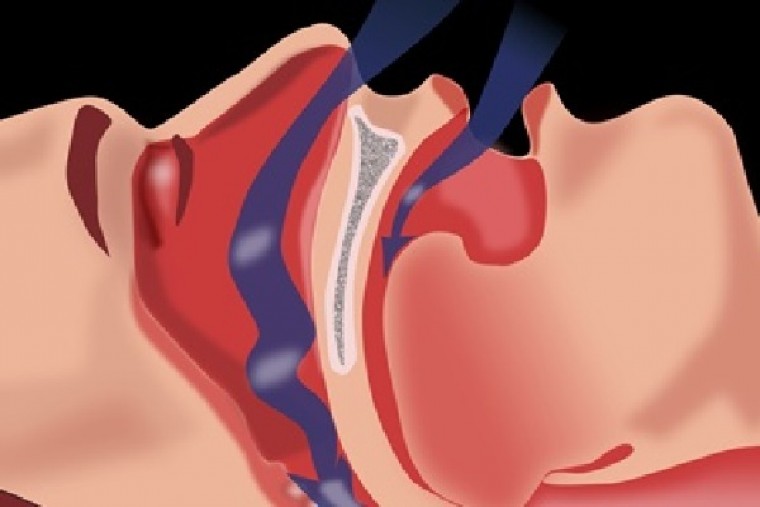

ఆస్ట్రేలియన్ పరిశోధన గురక, పెరిగిన రక్తపోటు మధ్య సంబంధాన్ని కనుగొంది